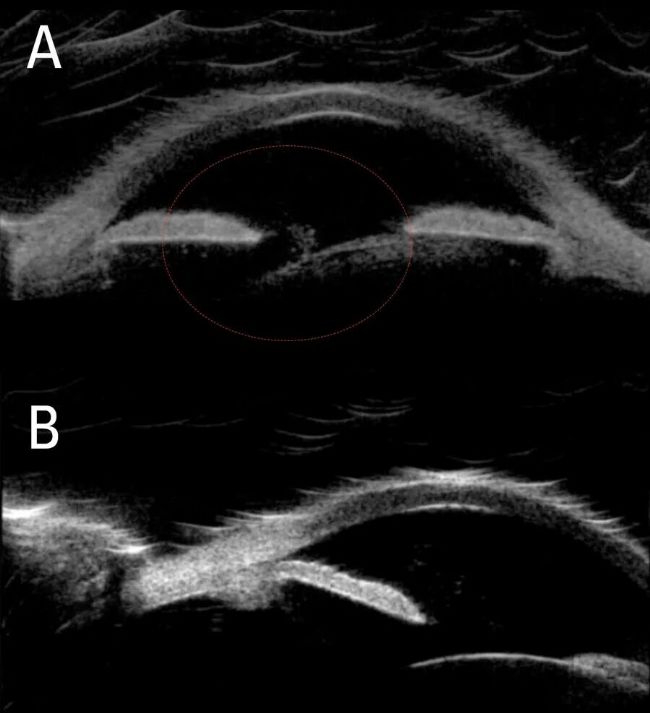

術(shù)前評(píng)估中,術(shù)中光學(xué)相干斷層掃描(OCT)顯示前房?jī)?nèi)存在玻璃體絮狀物(A)及嚴(yán)重傾斜的晶狀體(B)。一側(cè)睫狀溝空間缺失,另一側(cè)虹膜后方異常深陷,玻璃體由此處環(huán)繞。晶狀體活動(dòng)度極大,患者仰臥時(shí)房角會(huì)開(kāi)放。

術(shù)前術(shù)中 OCT 掃描顯示前房?jī)?nèi)玻璃體絮狀物(A)與嚴(yán)重傾斜的晶狀體(B)。影像由華盛頓大學(xué)醫(yī)學(xué)院 Arsham Sheybani 醫(yī)學(xué)博士提供。